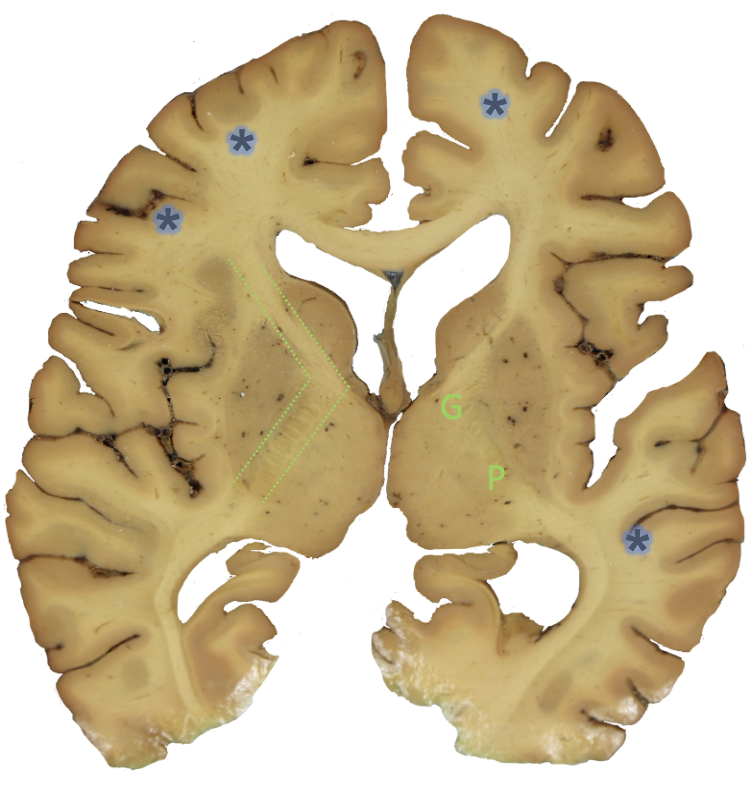

<p><strong>ic?</strong></p>

subcortical white matter

<p><strong>g?</strong></p>

genu

<p><strong>p?</strong></p>

posterior limb